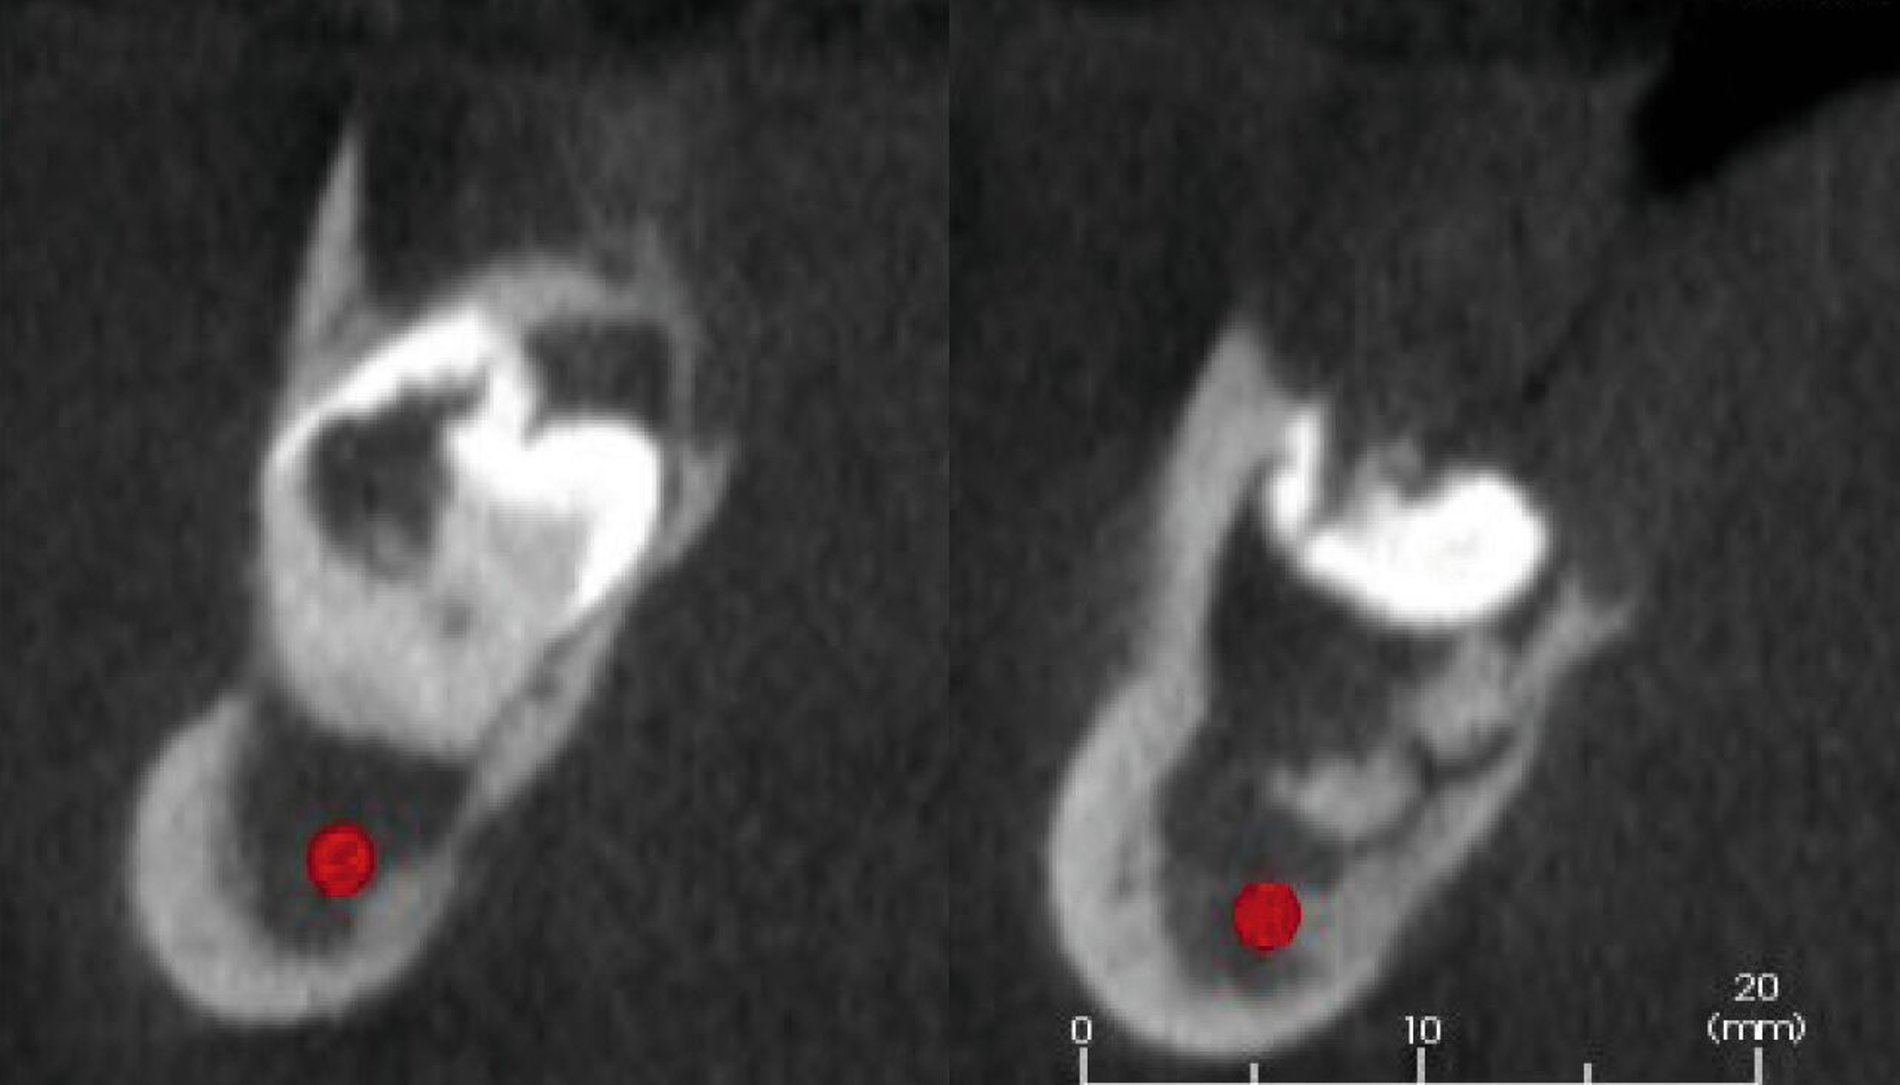

Zum Ausschluss einer Kieferwinkelfraktur bei verlagertem, doppelt angelegtem und infiziertem Weisheitszahn sowie zur Planung der späteren Rekonstruktion wird ein DVT angefertigt (Mesantis Berlin), das eine dehiszente knöcherne Abgrenzung zum pericoronalen Raum 48–49 im Kieferwinkel rechts mit kariösem Zahn 48 und Konkrement zeigt (Abbildung 4).

Nebenbefundlich ist für die spätere prothetische Rehabilitation in den sagittalen Schnitten zu erkennen, dass sowohl die scheinbare Knochenhöhe des anterioren Alveolarfortsatzes in Projektion der zweidimensionalen Aufnahme als auch die vermeintlich klinisch nutzbare Breite durch eine ‚bandnudelartige‘ diagonale Verdrillung der schmalen Knochenspange in beiden Ebenen nur vorgetäuscht sind (Abbildung 5).